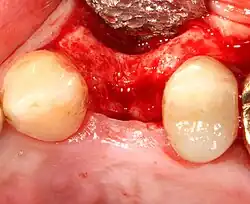

Placing the implant

Most implant systems have five basic steps for placement of each implant:[28]: 214–221

- Soft tissue reflection: An incision is made over the crest of bone, splitting the thicker attached gingiva roughly in half so that the final implant will have a thick band of tissue around it. The edges of tissue, each referred to as a flap, are pushed back to expose the bone. Flapless surgery is an alternate technique, where a small punch of tissue (the diameter of the implant) is removed for implant placement rather than raising flaps.

Timing of implants after extraction of teeth

There are different approaches to placement dental implants after tooth extraction.[55] The approaches are:

- Immediate post-extraction implant placement.

- Delayed immediate post-extraction implant placement (two weeks to three months after extraction).

- Late implantation (three months or more after tooth extraction).

An increasingly common strategy to preserve bone and reduce treatment times includes the placement of a dental implant into a recent extraction site. On the one hand, it shortens treatment time and can improve aesthetics because the soft tissue envelope is preserved. On the other hand, implants may have a slightly higher rate of initial failure. Conclusions on this topic are difficult to draw, however, because few studies have compared immediate and delayed implants in a scientifically rigorous manner.[55]